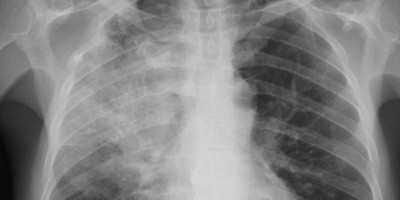

Підстав для масового призначення антибіотиків хворим на COVID-19 немає

Згідно з даними 24 клінічних досліджень, частка пацієнтів із COVID-19 та бактеріальними інфекціями склала 6,9%. При цьому антибіотики одержували 71,9% пацієнтів.